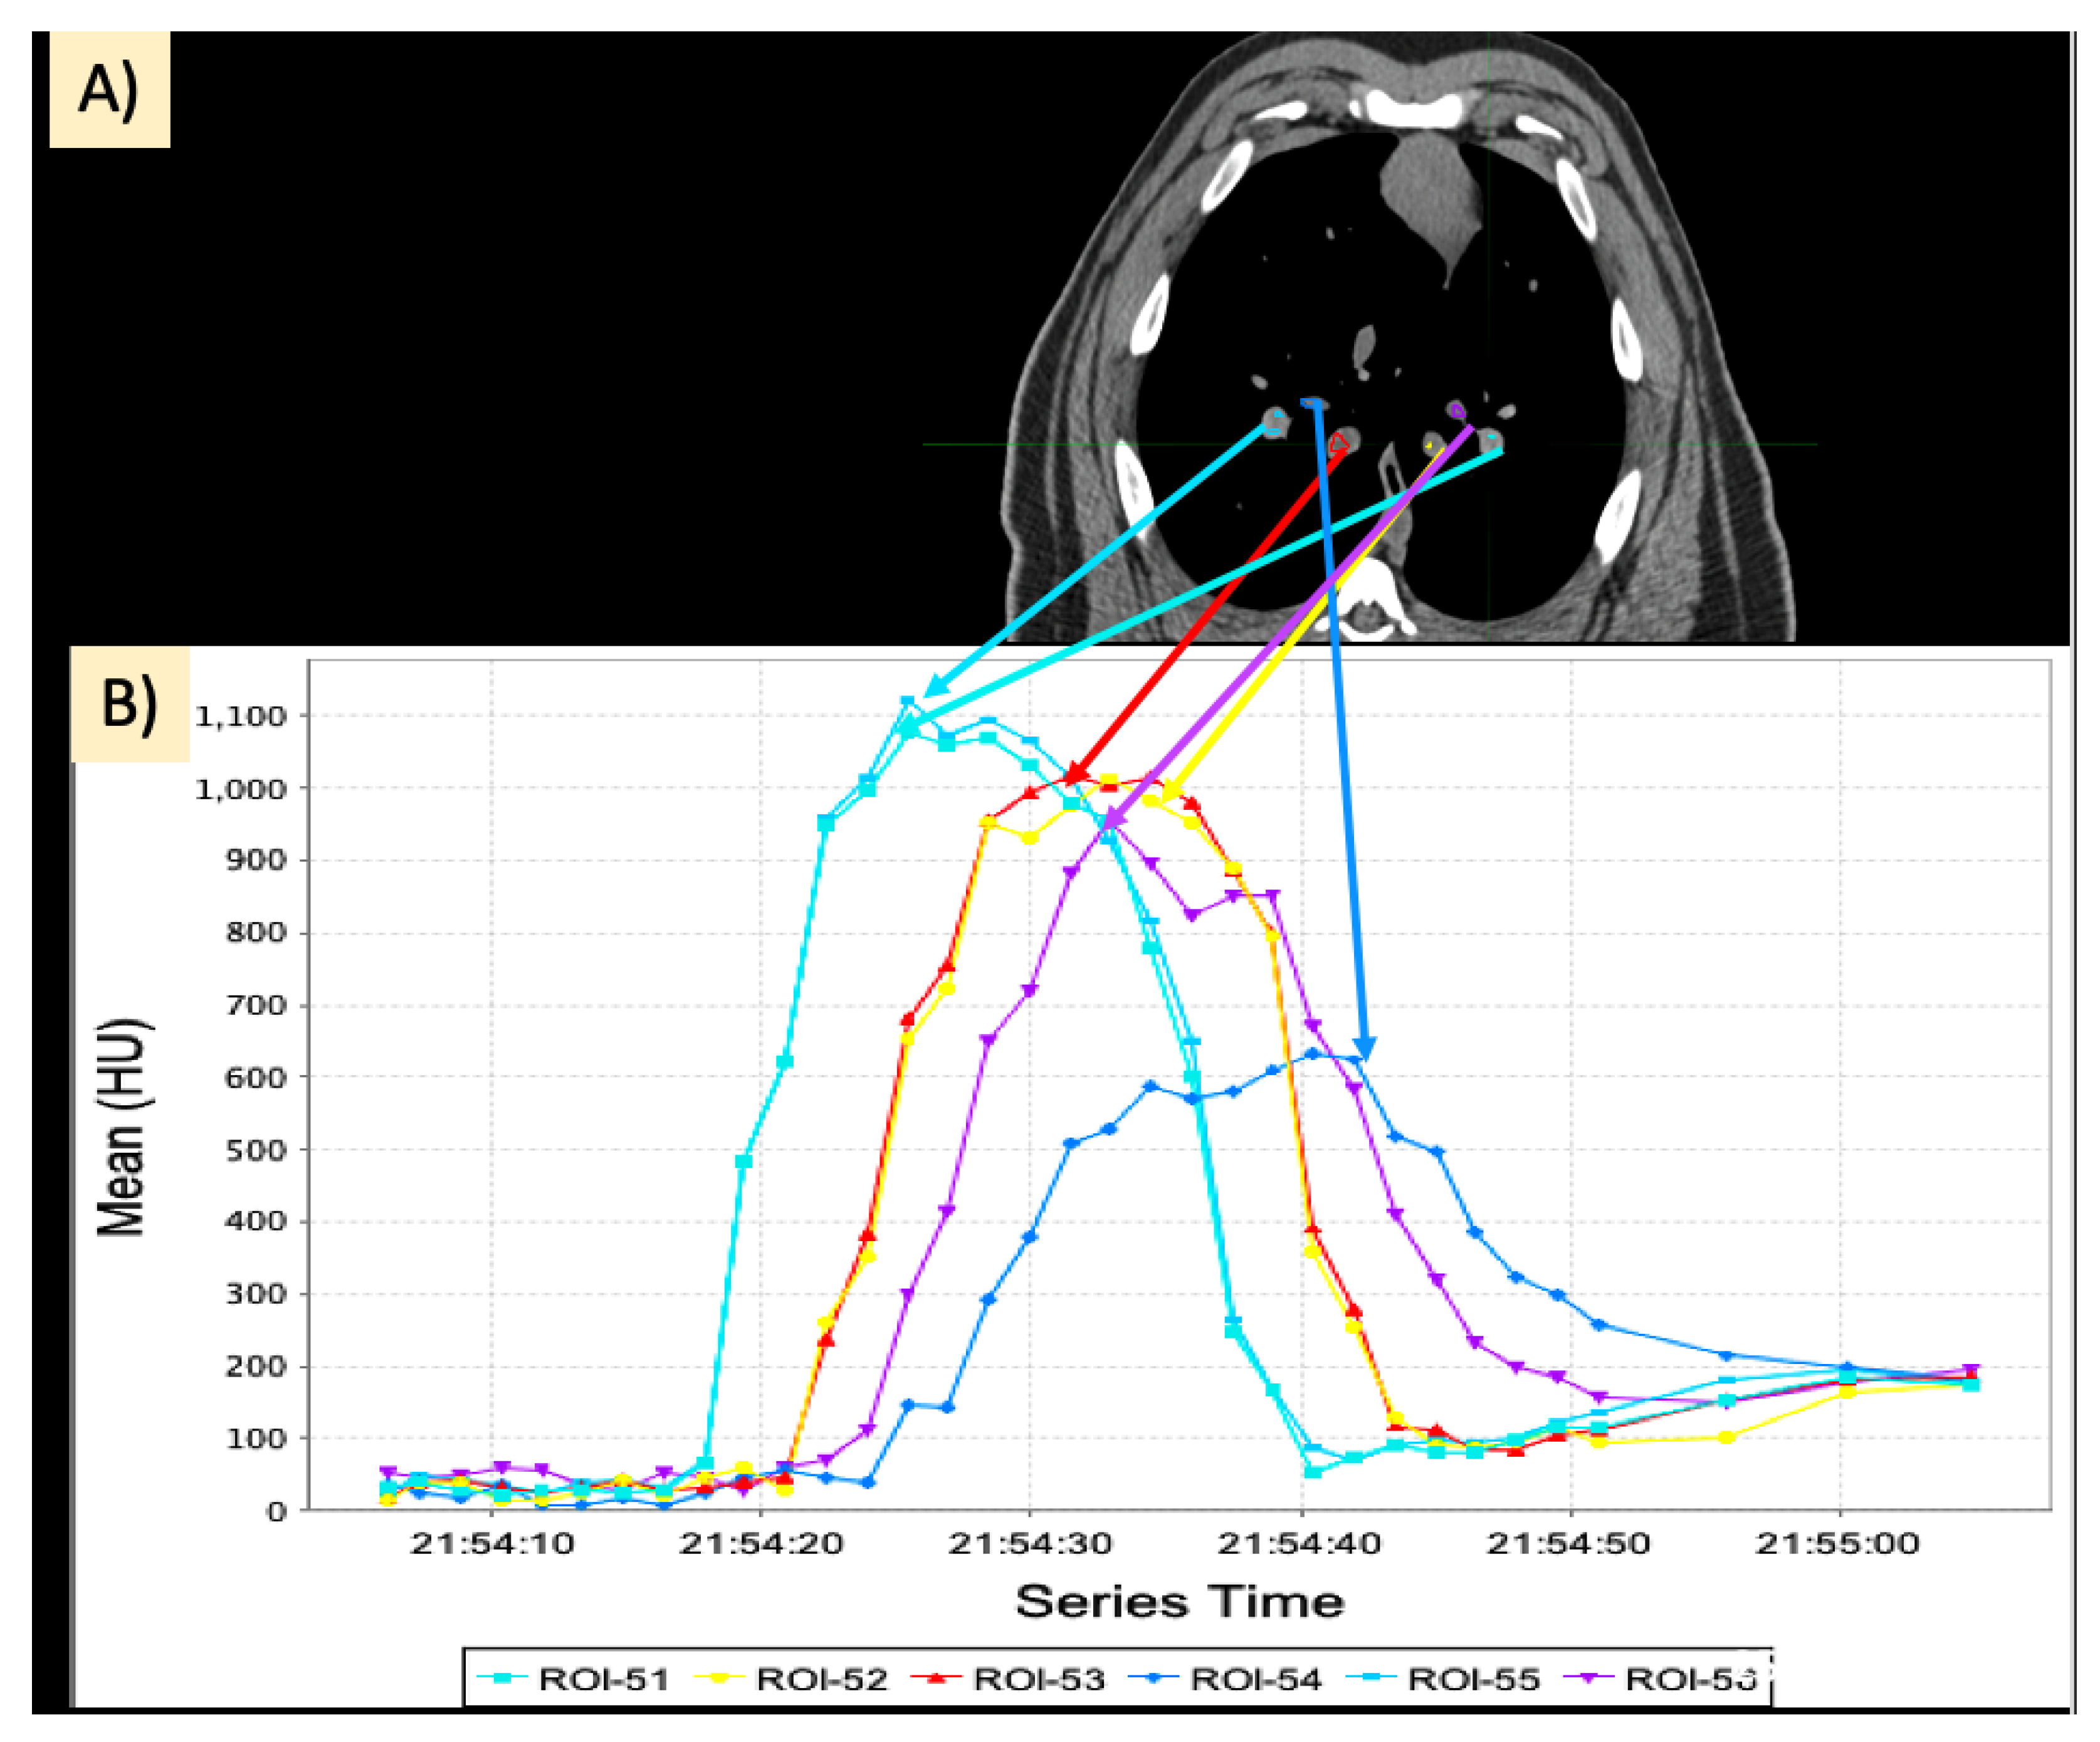

2.4. Dynamic Contrast CT

2.5. Regional Perfusion Analysis

2.5.1. Calculation of Slopes

2.5.2. Area under the Curve